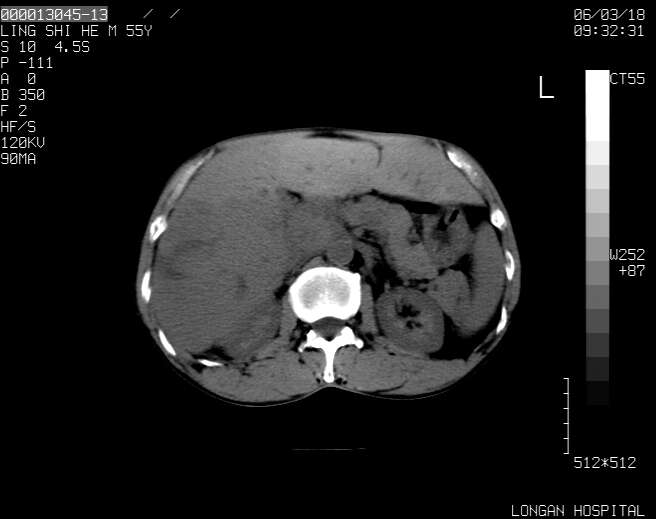

以下是引用guzhongliangddd在2006-3-21 22:13:00的发言:[br]病灶主要位于肝右叶的后份,内见异常血管,门脉主干及右支受侵{提示有癌栓形成},门腔间隙内见增大淋巴结。肝左叶内未见异常。

以下是引用zhuxinli在2006-3-22 1:23:00的发言:[br][br] 病灶主要位于肝右叶的后份,内见异常血管 .门脉右支截断,右叶前段早期强化(考虑动静脉漏),腹膜后肿大淋巴结,病灶逐渐强化,考虑为胆管细胞癌[br]